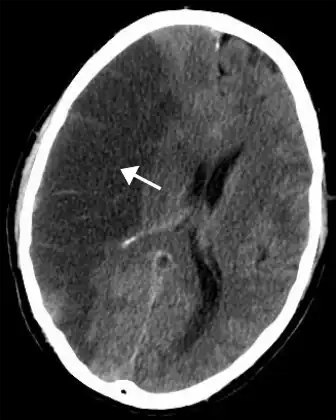

CT scan of the brain showing a prior right-sided ischemic stroke from blockage of an artery. Changes on a CT may not be visible early on.[1]

The main risk factor for stroke is high blood pressure.[6] Other risk factors include tobacco smoking, obesity, high blood cholesterol, diabetes mellitus, a previous TIA, end-stage kidney disease, and atrial fibrillation.[2][6][7] An ischemic stroke is typically caused by blockage of a blood vessel, though there are also less common causes.[12][13][14] A hemorrhagic stroke is caused by either bleeding directly into the brain or into the space between the brain's membranes.[12][15] Bleeding may occur due to a ruptured brain aneurysm.[12] Diagnosis is typically based on a physical exam and supported by medical imaging such as a CT scan or MRI scan.[8] A CT scan can rule out bleeding, but may not necessarily rule out ischemia, which early on typically does not show up on a CT scan.[9] Other tests such as an electrocardiogram (ECG) and blood tests are done to determine risk factors and rule out other possible causes.[8] Low blood sugar may cause similar symptoms.[8]